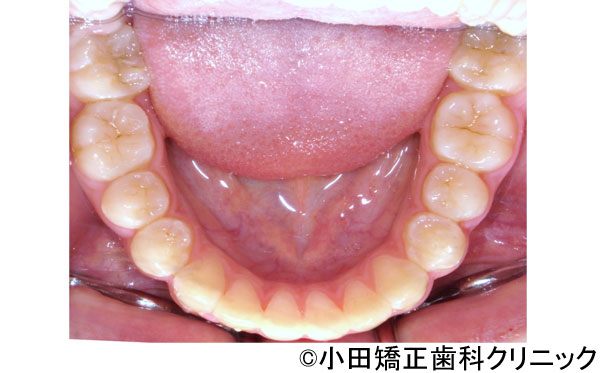

【症例4】口元が突出したいわゆる"クチゴボ"状態を、裏側(舌側)矯正で患者さんの期待を超えて治したい所を徹底的に治す治療

- 治療前

- 治療後

- 口元が突出したいわゆる"クチゴボ"状態を、裏側(舌側)矯正で患者さんの期待を超えて治したい所を徹底的に治す治療

- 患者様

- 26歳

- 費用

- 1,200,000円(税込)(上のみ舌側装置)

- 期間

- 2年

治療結果

-

美しい口元となり、顔全体とのバランスも良く、社会でコミュニケーションを図る時に人と面と向かって接する重要な顔立ちを大きく改善することができました。QOL(生活の質)を上げることができたと思います。治療が進んで顔立ちがきれいに変わっていくことで、診療室に入って来られても、最初の印象から誰だかすぐにわからないことがありました。